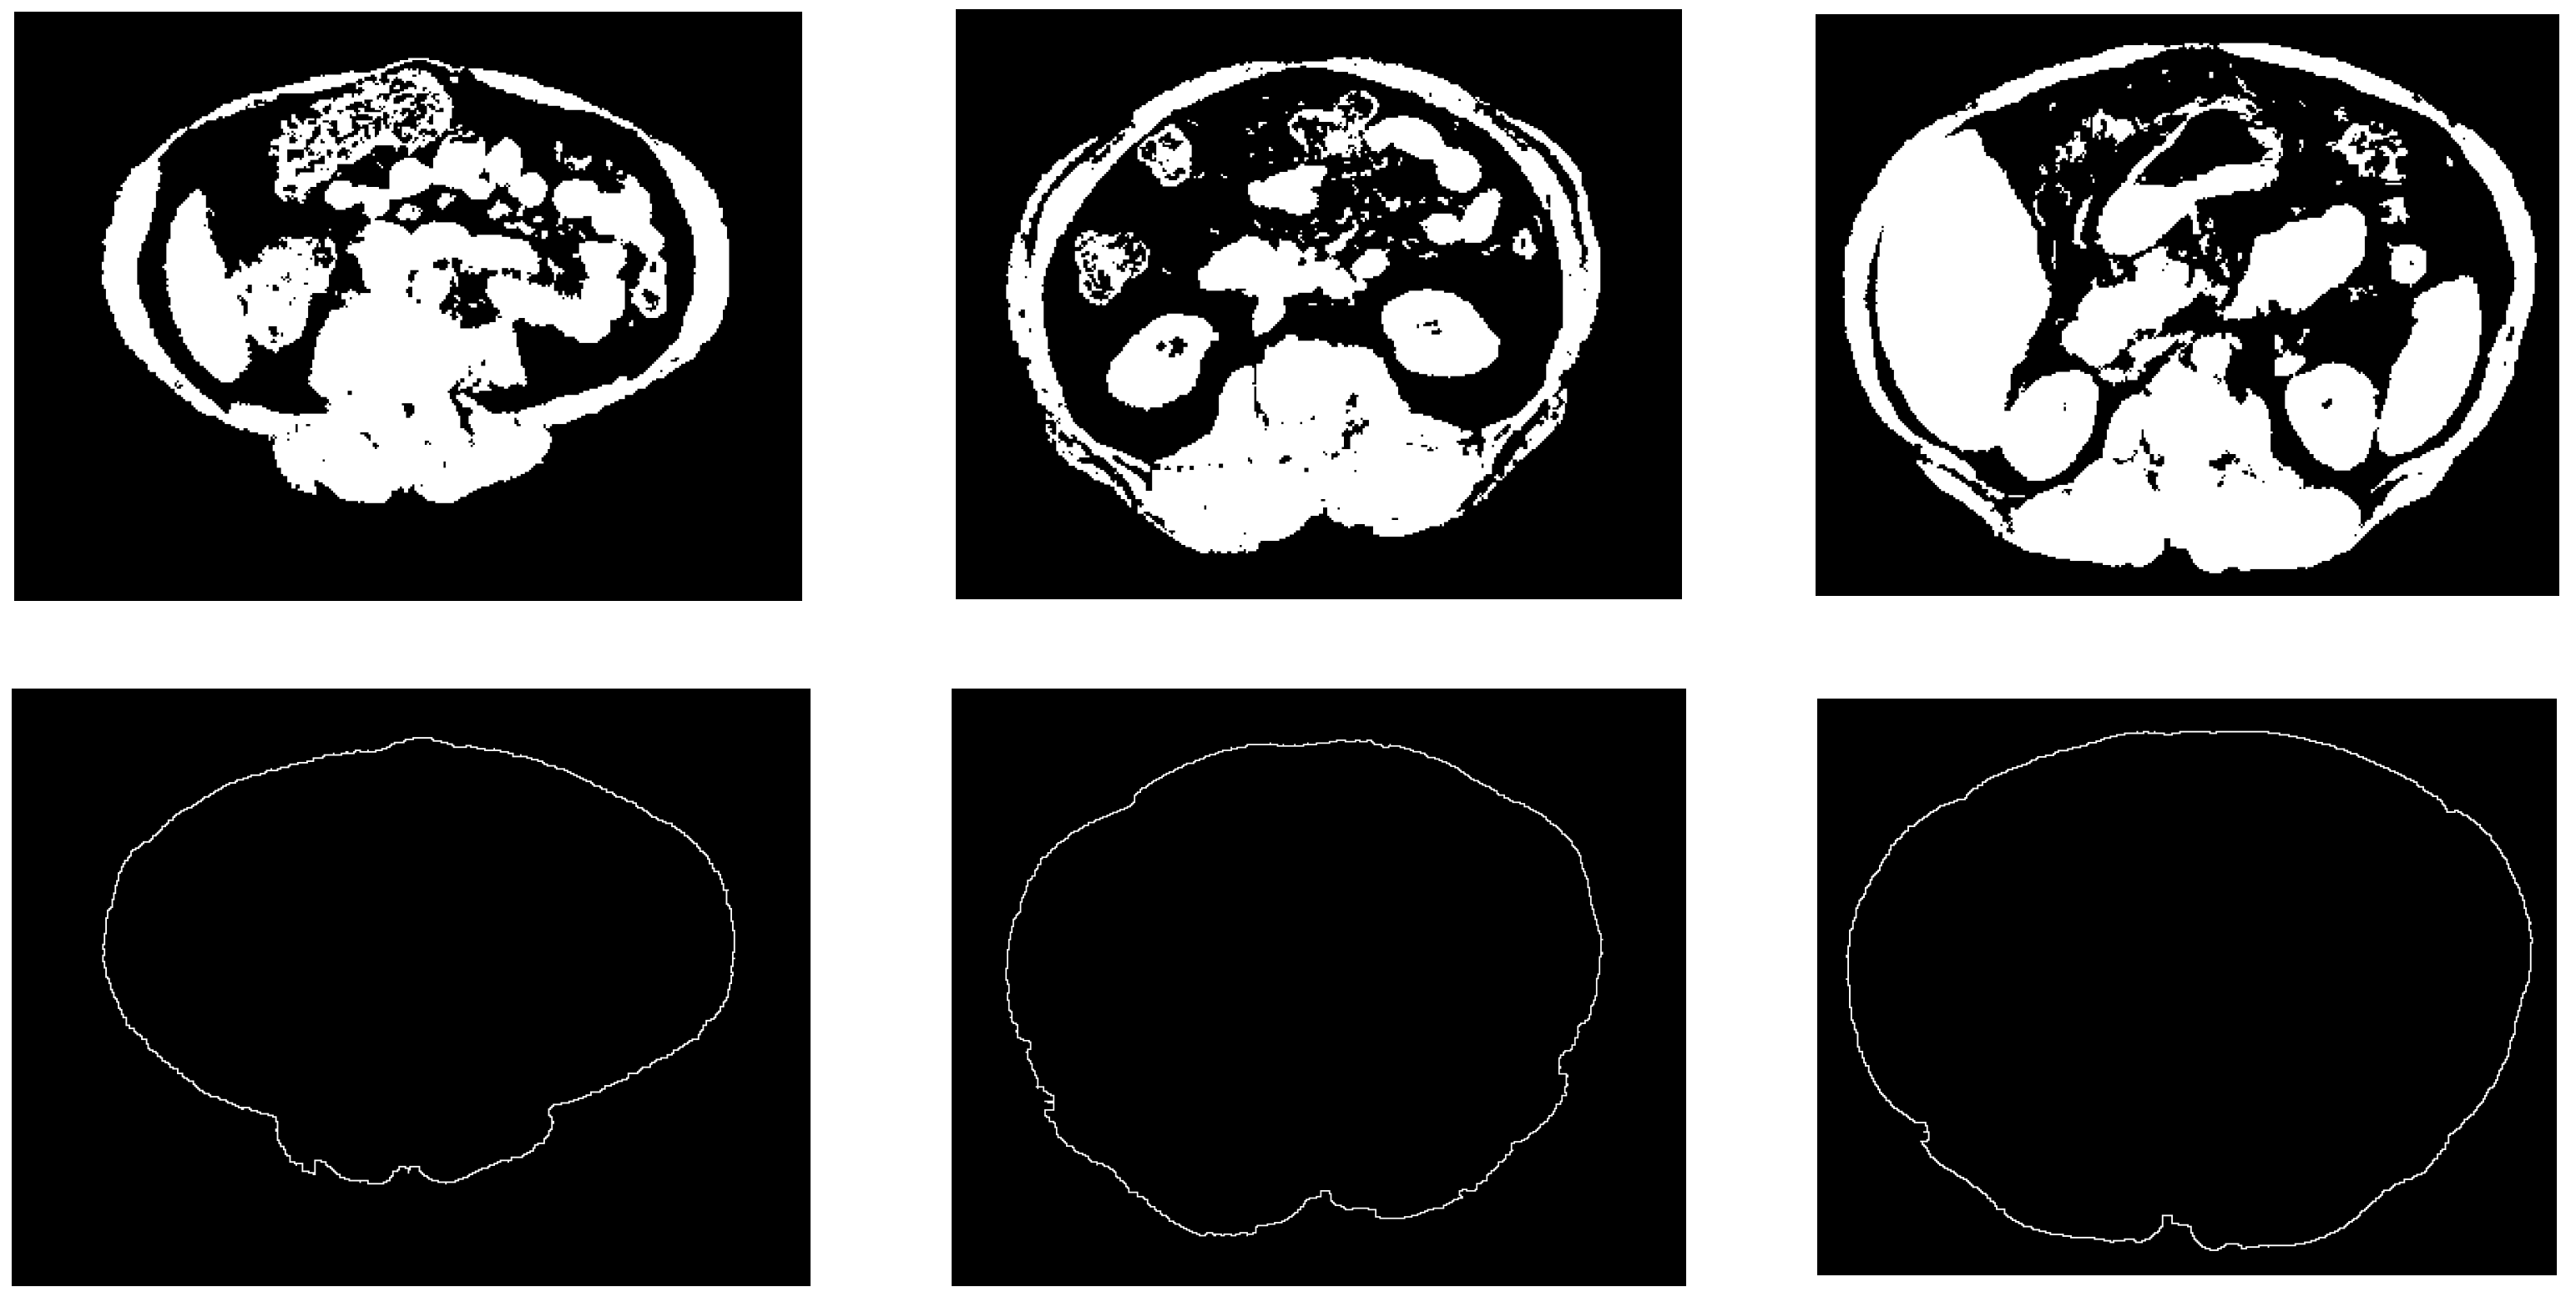

The automatic abdomen fat segmentation method used in this study is a robust method that is employed to detect and classify the abdominal fat in non-contrast-enhanced CT images. In this method, a modified fuzzy c-means (FCM) [25,26] clustering technique and the Otsu thresholding technique [27] were used to segment fat tissues. A non-fat binary image was used to detect and trace the boundary of the abdominal wall. This boundary was used to separate SF from VF. The process of detecting this boundary started with finding the boundaries of regions in a non-fat binary image (after removing the bed and any artificial elements that may appear). The non-fat binary image was scanned top to bottom, bottom to top, left to right, and right to left. During the scanning operation, whenever a foreground pixel was detected, the scanning in that line was terminated, and the detected pixel was considered as an abdomen wall boundary pixel. Every single pixel in this boundary image must be connected to two other pixels; if a pixel was detected with one or no connected pixels, it was connected to the nearest one or two boundary pixels.

Figure 7 shows some examples of the obtained results of the constructed abdominal wall using the proposed method.

Figure 7. Samples from the abdomen wall boundary detection results. The top row is the non-fat binary images, the bottom row is the abdomen wall boundary images.